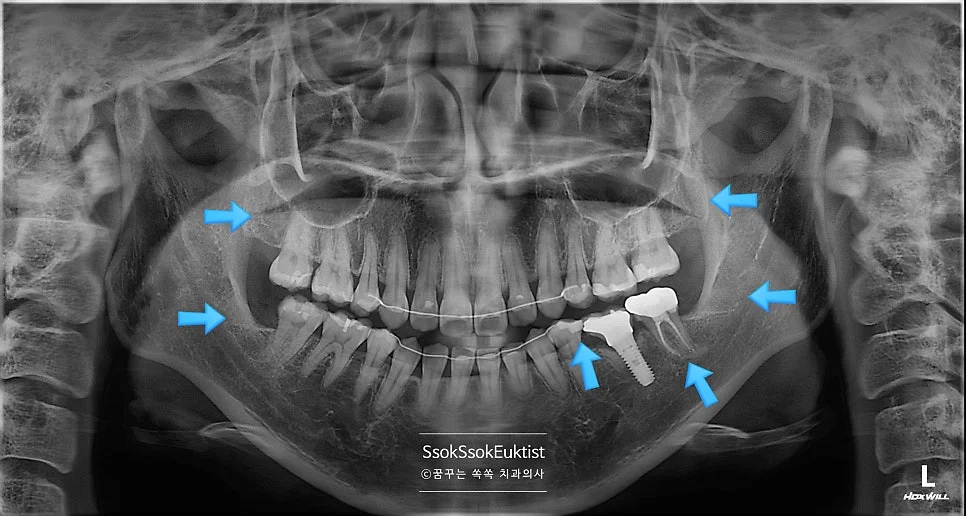

상악 사랑니 방사선 진단

상악 사랑니 — 크기가 작지만 비교적 얌전히 맹출

하악 매복 사랑니 충치 방사선 진단

하악 매복 사랑니 — 머리부터 충치가 진행된 상태

파란 화살표로 표시되어 있는 치아가 사랑니입니다! 위 사랑니는 크기가 좀 작지만 비교적 얌전히 나있는데요!

아래 두 개의 사랑니를 보면 머리부터 충치가 상당히 진행되어 있는 것을 볼 수 있습니다. 아래 사랑니는 매복 사랑니이기 때문에 발치를 해야 하고, 위 사랑니는 아래 사랑니를 제거하면 닿는 치아가 없어 필요 없고 관리만 안 되는 사랑니이기에 발치를 하는 것을 추천합니다!^^

매복 사랑니를 방치하면 바로 앞 치아에 충치 혹은 잇몸질환을 만들게 됩니다. 이것이 사랑니 발치를 꼭 해야 하는 가장 큰 이유입니다.